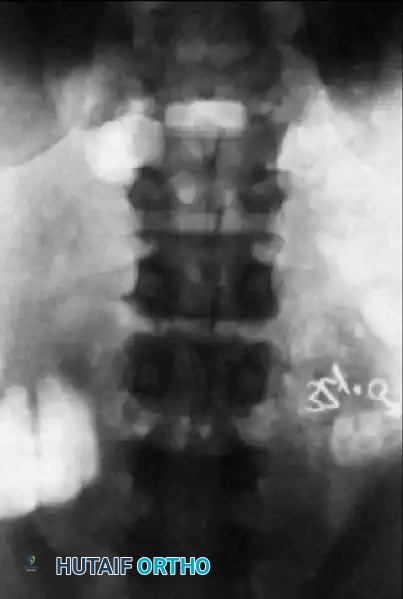

- Coronal Assessment: The AP view will reveal degenerative scoliosis, lateral olisthesis, and the status of the transverse processes.

Preoperative AP radiograph illustrating a degenerative lumbar scoliosis with lateral olisthesis and asymmetric disc space collapse.

- Ferguson View: A 30-degree cephalad-angled AP view of the lumbosacral junction is critical for visualizing L5-S1 degenerative changes and assessing the size of the L5 transverse processes. Hypoplastic transverse processes should prompt the surgeon to consider interbody fusion, as the posterolateral bone mass will be insufficient for a robust fusion mass.